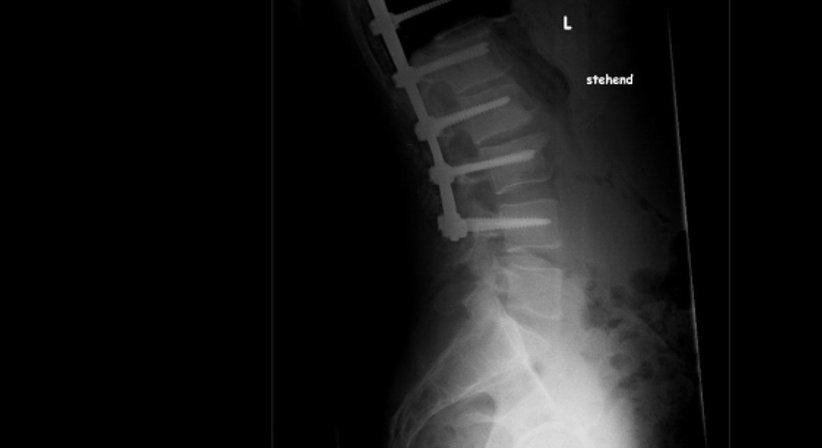

• Stabilisierende Eingriffe bei Instabilitäten durch frakturbedingte Deformitäten (z.b. posttraumatische Kyphose)